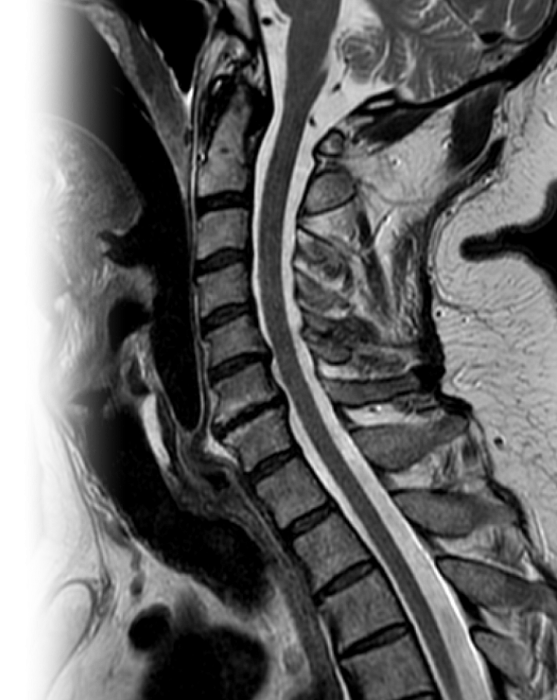

МРТ шейного отдела позвоночника МРТ шейного отдела позвоночника

МРТ шейного отдела позвоночника

Магнитно-резонансная томография шейного отдела позвоночника – важный метод исследования, который позволяет оценить состояние шейного отдела позвоночника.